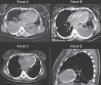

Una mujer de 28 años, previamente sana, fue ingresada en la unidad de cuidados intensivos con un diagnóstico de neumonía bilateral, derrame pleural y shock séptico. A su ingreso presentaba signos de hipoperfusión, así como obnubilación y presión arterial de 50/40mmHg. La tomografía computarizada (TC) mostró la presencia de neumonía y derrame pleural bilateral (fig. 1A: panel A). La paciente precisó soporte hemodinámico y ventilatorio, antibióticos de amplio espectro y drenaje pleural bilateral. Los resultados del líquido pleural fueron compatibles con empiema, y en el cultivo se aisló Klebsiella pneumoniae. Una nueva TC torácica, realizada al sexto día, evidenció importante mejoría de la condensación, disminución del derrame pleural y una inusual calcificación miocárdica1 (fig. 1B: panel B). Fue dada de alta de la UCI en condición estable, pero taquicárdica y con dolor torácico de características pleuríticas. Veinte días después se realiza una nueva TC de tórax, en la que se observa mínimo derrame pleural, mejoría de la condensación y un aumento de la calcificación que afecta al miocardio ventricular izquierdo2 (figs. 1C y D: panel C). La fisiopatología de la calcificación miocárdica no está completamente explicada, pero suele representar la secuela de un daño tisular local, alteración de la membrana o necrosis celular y no guarda relación con alteraciones en los niveles o en el metabolismo del calcio. La etiología más frecuente es el infarto de miocardio, aunque también se ha reportado en el contexto de traumas, infecciones, procesos inflamatorios o neoplásicos3.

A) Tomografía de ingreso, que muestra la presencia de derrame pleural bilateral y consolidaciones pulmonares. B) Similar corte tomográfico realizado 7 días después, donde destaca el miocardio ventricular calcificado. C y D) Calcificación extensa de todo el miocardio ventricular izquierdo (día 30).